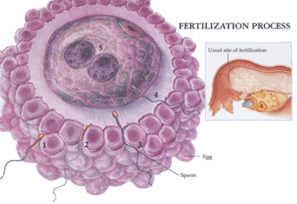

Fertilizing the eggs

Once the eggs are harvested and cleaned in the laboratory, your embryologist will fertilize them with the fresh or frozen sperm of the intended sperm source.

The two methods of egg fertilization

There are two methods your doctor can use to fertilize the egg. The process used on the day of your retrieval will depend on your doctor's recommendation. Here are the two methods of egg fertilization available at PFCLA:

- Most commonly, your doctor will recommend the use of the ICSI methodology. Intracytoplasmic Sperm Injection is when the embryologist carefully fertilizes each egg by injecting a single, healthy sperm to increase the rate of fertilization.

- In some instances, your doctor may recommend the eggs be fertilized by incubation with the collected sperm overnight in a petri dish. This is a simpler method, but is somewhat dependent on the health and quantity of sperm, as well as the health of the retrieved / thawed eggs.

Note: ICSI is sometimes the only means to achieve fertilization, especially in severe male infertility factor cases.

Roughly 16 hours after insemination, your embryologist will examine the fertilized eggs. A fertilized egg is called an embryo, which goes through stages of development until it’s ready for transfer to the uterus.